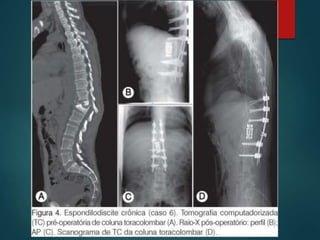

Tomografia computadorizada

 Permite avaliar o anel ósseo que circunda

o canal vertebral.

 Ident áreas de compressão medular

 Visualização das estruturas posteriores.

 Pode ser feita sem mobilização do

paciente. (bom frat instáveis)

Tratamento cirúrgico.  Abordagemanterior é indicada para suporte anterior do segmento vertebral e descompressão do canal vertebral insuficiente.( A1,A2, técnica isolada ou associada)  Nas fraturas tipo B e C a abord anterior pode se associada a posterior.  Entre T10 e L2 abordagem toracoabdominal ( acesso anterolateral) ↑ morbimortalidade.  Entre T12 E L1 Abordagem transpleural retroperitonial retirada da 10º costela.